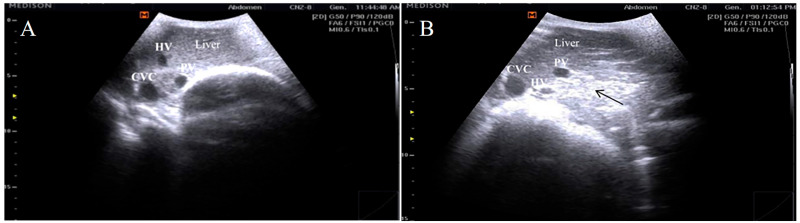

妊娠毒血症(妊娠毒血症)是一种影响小反刍动物的重要代谢紊乱,由于生产力下降、繁殖失败和高死亡率而造成重大经济损失。研究了沙米山羊PT易感性的临床、超声、血液生化、氧化应激和免疫学特征,以及与PT易感性相关的基因表达和核苷酸序列变异。对50例晚期妊娠妇女(33例健康,17例pt影响)进行了检查。进行临床评价、全血计数、生化分析、细胞因子谱分析、抗氧化检测、肝脏超声检查、免疫(IL6、IL8)、抗氧化(SOD3、HMOX1)和脂肪生成(ACACA、FASN)基因的实时定量PCR检测,以及PCR- dna测序。PT确实表现出明显的低血糖、高酮血症、肝肾功能生物标志物升高、血脂异常、氧化应激(↑MDA、↓GSH、GPx、SOD、CAT)、促炎细胞因子(IL1α、IL1β、IL6、TNFα)升高和IL10降低。基因表达分析显示,PT中IL6和IL8表达上调,SOD3、HMOX1、ACACA和FASN表达下调。测序发现多个同义和非同义snp与PT显著相关。超声检查显示肝脏脂肪浸润。使用SNPs的判别分析在健康和PT之间的分类准确率达到100%。这些结果表明,结合临床、生化、氧化、免疫和遗传标记可提高PT的早期诊断,并可为未来的选择性育种研究提供基础。

Pregnancy toxemia (PT) represents a significant metabolic disorder affecting small ruminants that causes substantial economic losses due to reduced productivity, reproductive failure, and high mortality. This study investigated the clinical, ultrasonographic, hematobiochemical, oxidative stress, and immunological profiles, as well as the gene expression and nucleotide sequence variations, associated with PT susceptibility in Shami goats. Fifty late-pregnant does (33 healthy and 17 PT-affected) were examined. Clinical evaluation, complete blood count, biochemical analysis, cytokine profiling, antioxidant assays, hepatic ultrasonography, quantitative real-time PCR of immune (IL6, IL8), antioxidant (SOD3, HMOX1), and lipogenic (ACACA, FASN) genes, and PCR-DNA sequencing were performed. PT does exhibit significant hypoglycemia, hyperketonemia, elevated liver and kidney function biomarkers, dyslipidemia, oxidative stress (↑ MDA, ↓ GSH, GPx, SOD, CAT), increased pro-inflammatory cytokines (IL1α, IL1β, IL6, TNFα), and reduced IL10. Gene expression analysis revealed upregulation of IL6 and IL8 and downregulation of SOD3, HMOX1, ACACA, and FASN in PT does. Sequencing identified multiple synonymous and non-synonymous SNPs significantly associated with PT. Ultrasonography indicated hepatic fatty infiltration. Discriminant analysis using SNPs achieved 100% classification accuracy between healthy and PT does. These findings suggested that combined clinical, biochemical, oxidative, immunological, and genetic markers could enhance early PT diagnosis and may provide a basis for future studies aimed at selective breeding for improved resistance.